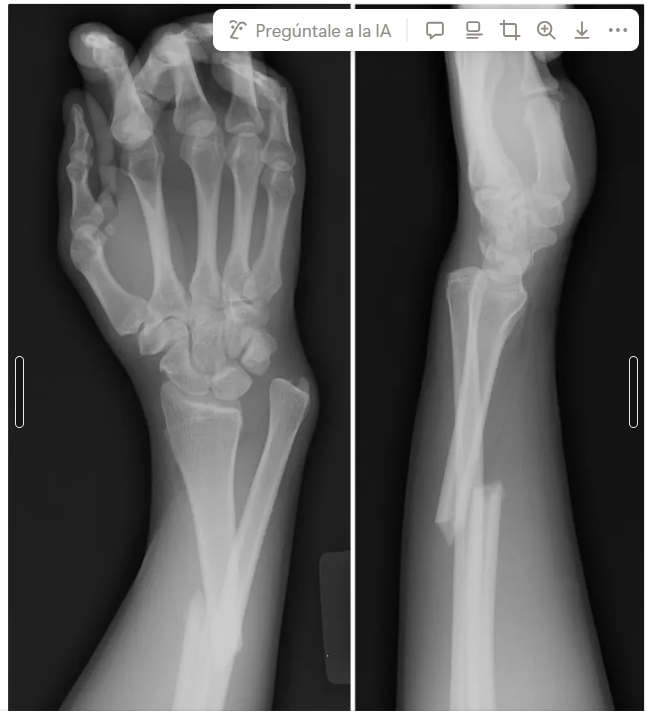

Px de 23 años jugando americanos cayo con mano y codo en extensión

Fx de radio distal y luxación radio cubital distal = Galiase